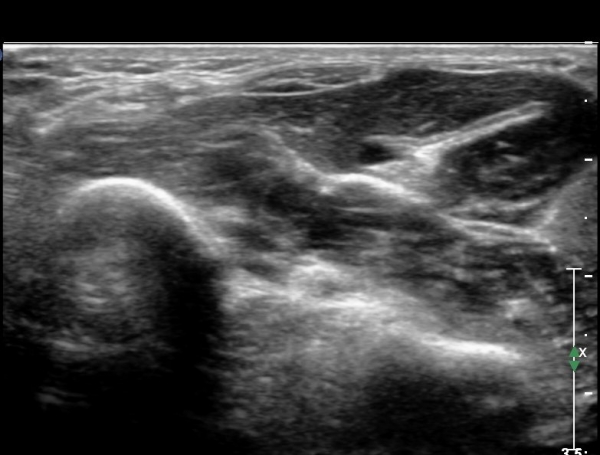

¾Æ·§ÆÈ »óºÎ Ⱦ´Ü¸é°Ë»ç¿¡¼­ Àü°ñ°£ ½Å°æ Áö¹è¸¦ ¹Þ´Â FPL, FDP ¿¡¼­ ½Å°æ¸¶ºñ ¼Ò°ß(°í¿¡ÄÚ ±ÙÀ§Ãà)À»

º¸ÀÌÁö ¾ÊÀ½(»çÁø 1)